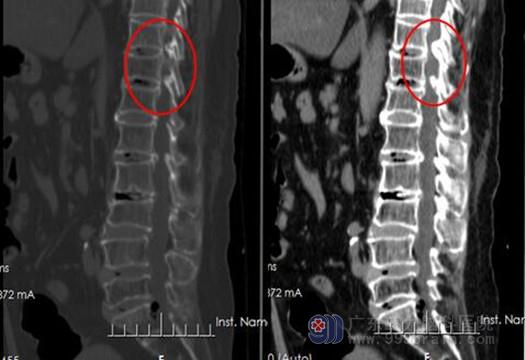

黄韧带骨化CT